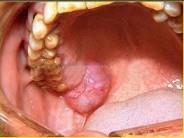

问题 以下关于黏液表皮样癌(如图)的叙述中,哪项是错误的()

选项 A.女性多于男性,发生于腮腺者居多 B.高分化黏液表皮样癌很少发生颈淋巴结转移 C.低分化黏液表皮样癌淋巴结转移率高 D.高分化和低分化者均应作选择性颈清 E.高分化黏液表皮样癌较低分化黏液表皮样癌常见

答案 D